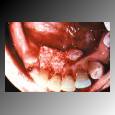

Cancer of the Mouth